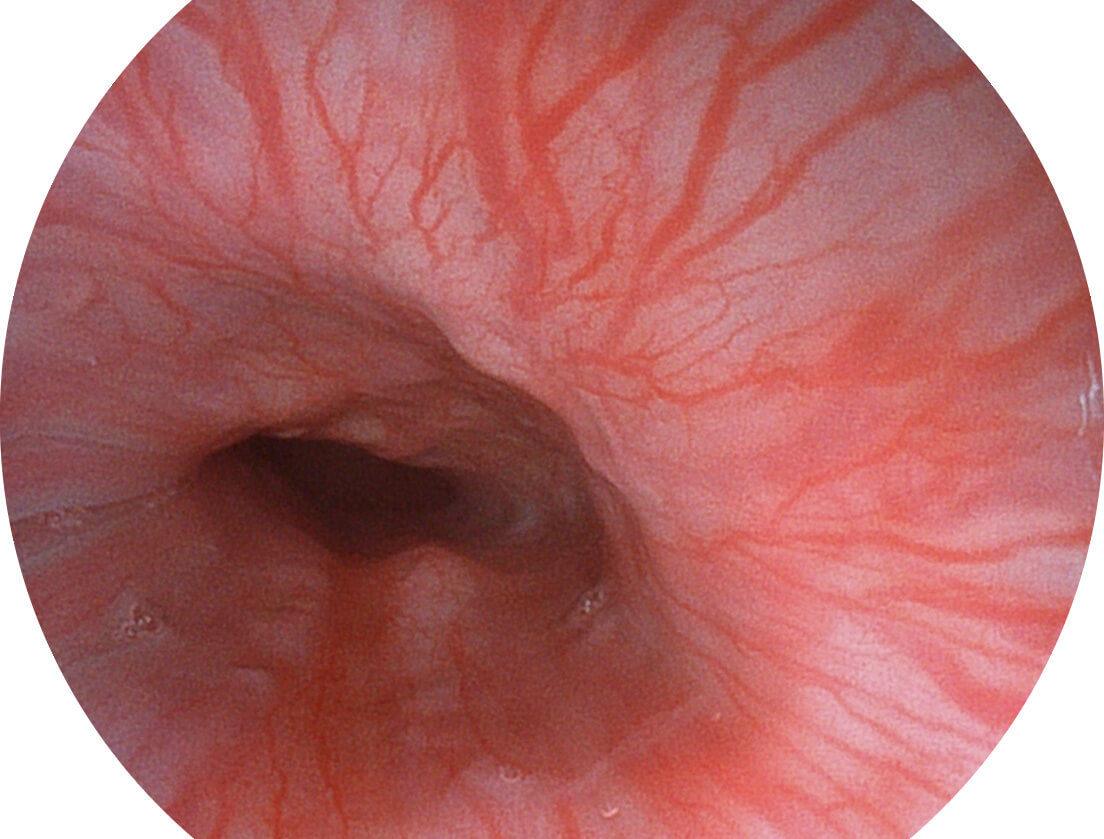

白光图像

采用光路合束技术,光谱自由度高,实现了更丰富的照明模式,染色模式SFI及VIST,从远景到近景,助力消化道早期疾病诊断。